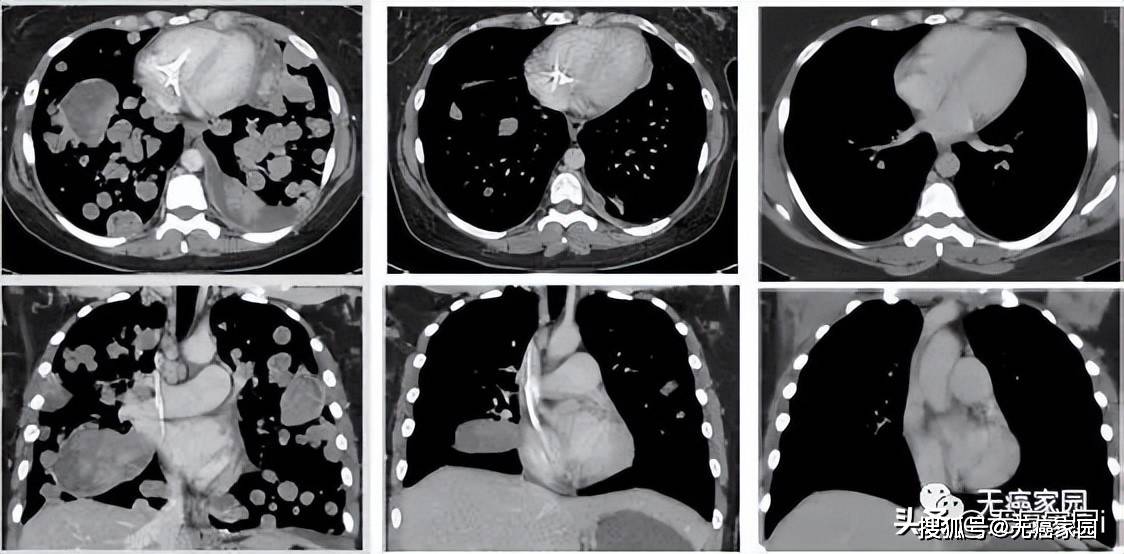

典型病例066:肺癌肺转移,密集恐惧症者忌 [病例帖]

小细胞肺癌伴全身多发转移化疗1例

怀疑左下肺癌,但入院一做检查就发现脑部,肝,全身骨多发转移病灶